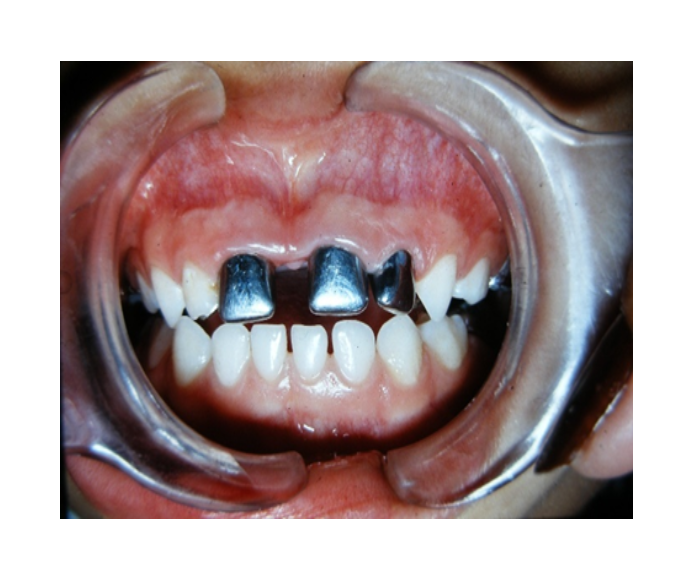

Mordida Cruzada posterior unilateral